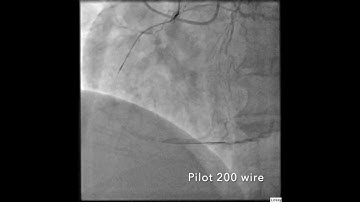

Retrograde LCX CTO PCI Through Venous Graft By Dr. Sharath Reddy